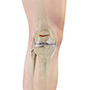

Bones of the Knee

The knee is a hinge joint made up of two bones, the thighbone (femur) and the shinbone (tibia). There are two round knobs at the end of the femur called femoral condyles which articulate with the flat surface of the tibia called the tibial plateau. The tibia plateau on the inside of the leg is called the medial tibial plateau, and on the outside of the leg it is called the lateral tibial plateau.

The two femoral condyles form a groove on the front (anterior) side of the knee called the patellofemoral groove. A small bone called the patella sits in this groove and forms the kneecap. It acts as a shield and protects the knee joint from direct trauma.

A fourth bone called the fibula is the other bone of the lower leg. This form a small joint with the tibia. This joint has very little movement and is not considered a part of the main joint of the knee.